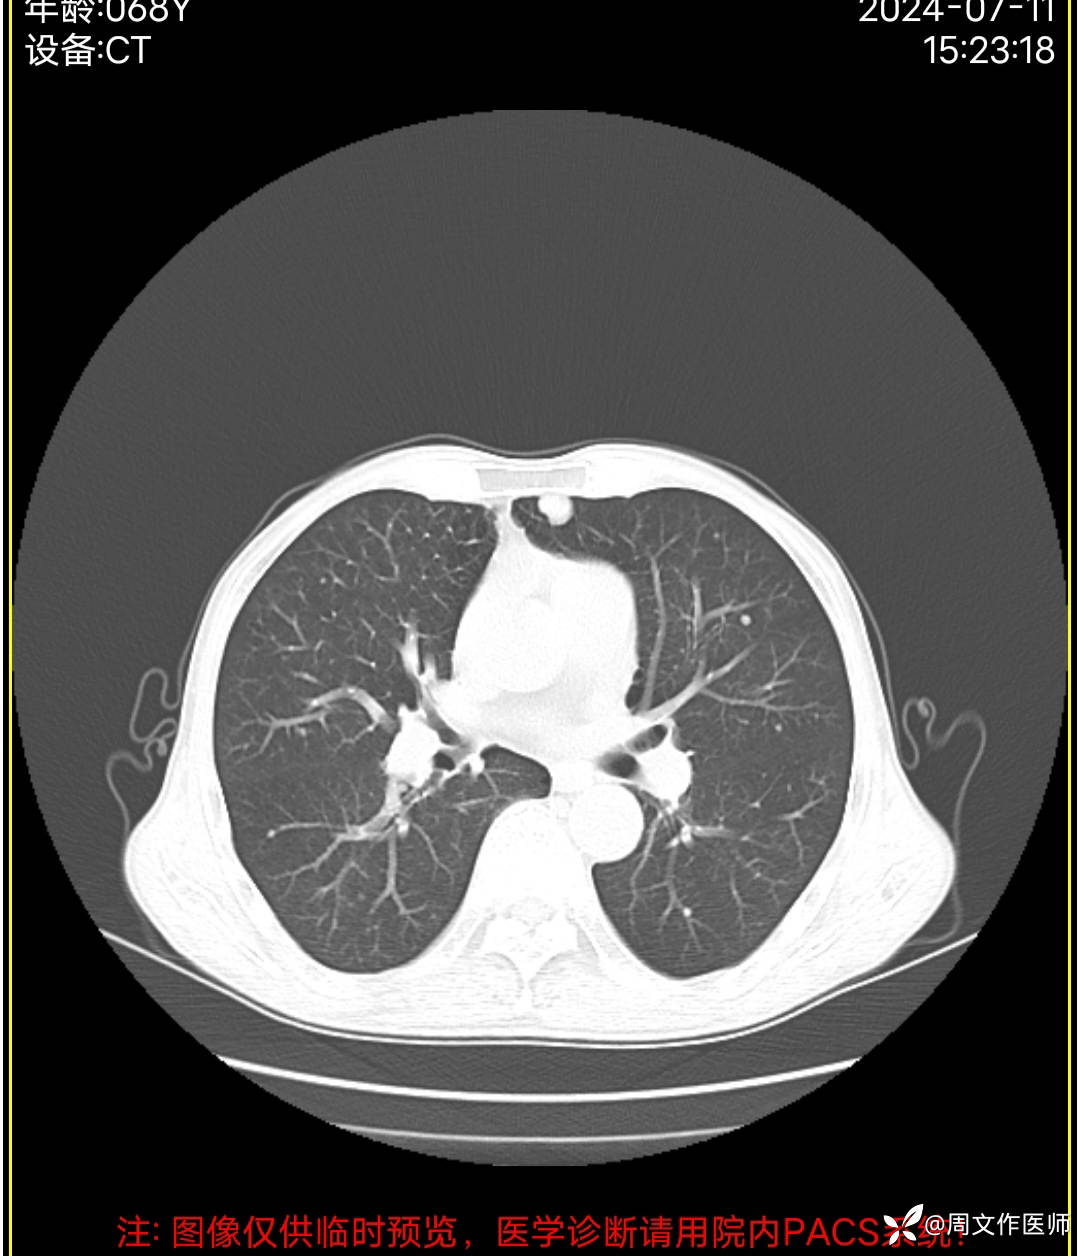

胸部CT检查